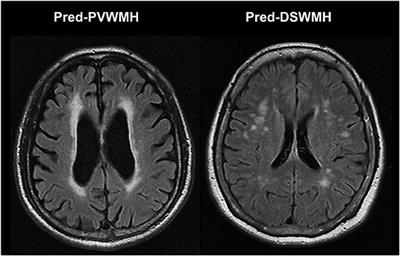

It can affect fetuses or newborns. This can cause a slight decrease in the white matter of the brain. Web The scale divides the white matter in periventricular and deep white matter and each region is given a grade depending on the size and confluence of lesions 1. Periventricular white matter lesions and lacunar infarcts.

Web Periventricular leukomalacia or PVL is a type of brain damage that involves the periventricular white matter of the brain. Web Most MS findings take place inside the white matter and lesions appear mainly in a periventricular distribution clustered around the ventricles of the brain. Web Periventricular white matter lesions can be seen the white spots towards the bottom. Although substantiation is required a small study of patients with major depressive disorder has suggested the presence of a greater number of.